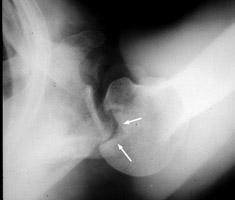

Posterior shoulder dislocation

Trough line is seen with posterior shoulder dislocation. When the humeral head is forced posteriorly in internal rotation, the anterior aspect of the humeral head is driven against the posterior glenoid rim. With sufficient force, the head will sustain a compression fracture. In many cases of posterior dislocation of the shoulder, two parallel lines of cortical bone can be seen. The outer (more medial) cortical line represent the medial cortex of the humeral head, while the other line represents the margin of a "trough" like impaction fracture.

bulletCisternino SJ, Rogers LF, Stufflebam BC, Kruglik GD: The trough line: a radiographic sign of posterior shoulder dislocation. AJR Am J Roentgenol 1978 May;130(5):951-4.          [See related articles]